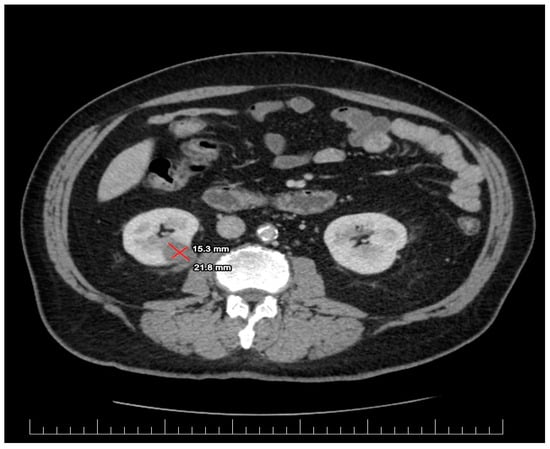

2. Case Presentation

2.1. Diagnostic Assessment